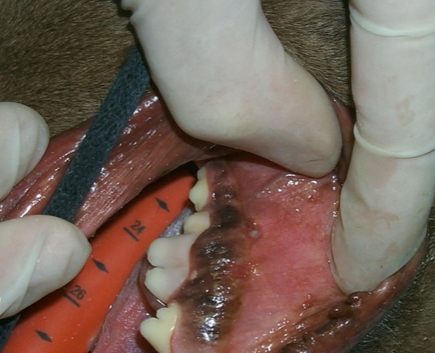

Q

DX?

A

fistule a/n de la muqueuse (ligne muco-gingivale)